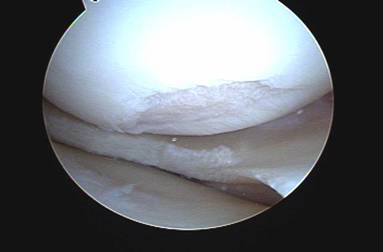

The cartilage surfaces behind the kneecap are the thickest in the entire human body and usually begin to wear out after the age of 15. Almost all people have evidence of cartilage damage on kneecap cartilage when we perform arthroscopic surgery. It is interesting to note however that while the pain from chondromalacia is the most common complaint of people between the ages of 15 and 60, these complaints usually disappear after age of 60. In addition, most persons with chondromalacia do not have symptoms.

The most common medical finding is damage to the cartilage behind the kneecap (patella). The cartilage covering, or articular cartilage, that covers the knee cap bone is the thickest cartilage covering in the entire human body. The reason the cartilage covering in this area is so thick is because the knee cap takes more pressure per unit of area than any other joint in the body. With squatting and lunging activities up to six times the body weight is placed into the small bone of the knee cap and the cartilage. With activities this cartilage can begin to breakdown and produce pain.

When exercises fail to improve the knee then surgery may be indicated if the symptoms are significant enough to alter activities. The most common arthroscopic surgical procedures to treat chondromalacia include chondroplasty and microfracture / abrasion procedure. A chondroplasty involves smoothing out roughened surface cartilage which can decrease friction forces on the surface cartilage and decrease symptoms of chondromalacia. An abrasion or microfracture is most useful when there is a small contained area of exposed bone or complete loss of surface cartilage. During this procedure the bone is tapped with a pick-type tool which causes bleeding in the area of exposed bone. This blood from deep inside the bone carries stem cells which can cause the bone to grow a scar type cartilage. This scar cartilage has been shown to be very effective in reducing knee pain in several orthopedic studies.